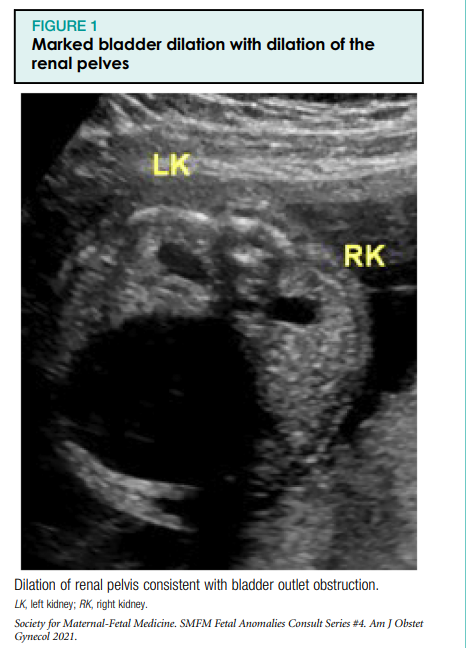

Sünnieelselt tuvastatud LUTO tekib areneva loote alumiste kuseteede (põie väljalaskeava) ummistumise tõttu ja põhjustab megatsüsti, paksenenud põieseina ja kahepoolset hüdroonefroosi koos neeruparenhüümi tsüstilise düsplaasiaga või ilma.

In the first trimester of pregnancy, megacystis, or an enlarged bladder, is commonly defined as a sagittal length >7 mm.1e3 After the first trimester of pregnancy, there is no single definition of megacystis, with many different definitions found in the literature.4 One study defined the normal sagittal length as the gestational age in weeks minus 5 mm (95% upper or lower confidence interval [CI]¼7); megacystis was defined as greater than the upper limit of the 95% CI for the gestational age.5 A thickened bladder wall is defined as one that measures >3 mm. Hüdronefroos on defineeritud kui neeruvaagna laienemine, mõõdetuna anteroposterioorses läbimõõdus, 4 mm raseduse teisel trimestril ja 7 mm raseduse kolmandal trimestril (joonis 1). Laienenud tagumine ureetra, tuntud ka kui "võtmeaugu" märk, on tavaliselt seotud tagumiste kusiti klappidega (joonis 2). Lisaks võib kõrgest põierõhust tingitud tagasivoolu tõttu täheldada kusejuha laienemist. Neerud võivad välja arendada tsüstilise düsplaasia või muutuda ehhogeenseks ja atrofeeruda.